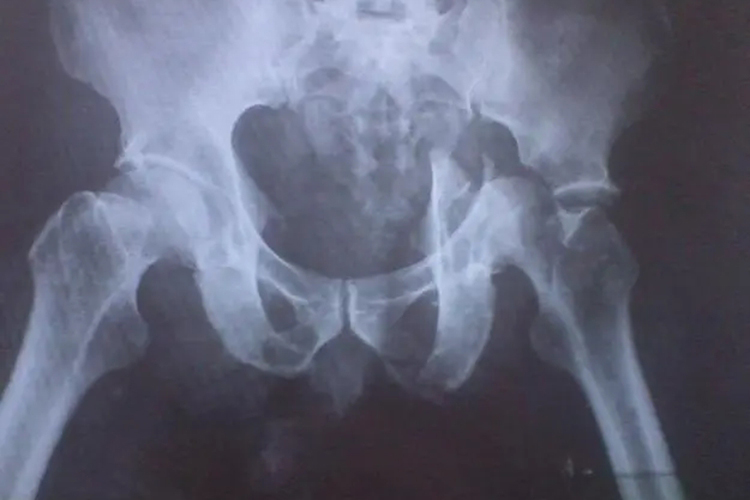

髋关节脱位包括后脱位、前脱位、中心性脱位,三者症状略有区别,临床常见后脱位。

后脱位:可出现患侧臀部膨隆肿胀,大粗隆上移,髋臼前方空虚,可在髂坐线后上方扪及股骨头。外观髋、膝关节轻度屈曲,呈内收内旋畸形。

前脱位:前脱位可在髂坐线的前方,即闭孔或耻骨上支处扪及股骨头,患肢髋关节轻度屈曲,呈外展外旋畸形。

中心性脱位:中心性脱位轻者畸形不明显,重者下肢短缩,且伴有大粗隆内移消失。做肛门指诊可扪及脱至盆腔内的股骨头。